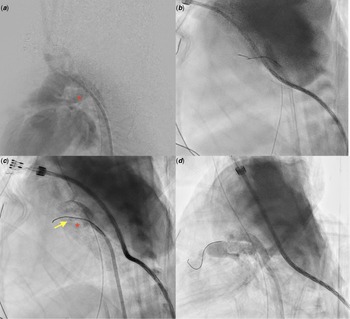

A newborn (gestational age 37 + 5 days, birth weight 2676 g) was found to have cyanosis (pulse oximetry 75%) upon birth. Echocardiography resulted in diagnoses of pulmonary atresia with intact ventricular septum, right ventricle hypoplasia, and patent ductus arteriosus. Continuous prostaglandin E1 was administered immediately. CT angiography confirmed the diagnosis. Transcatheter valvotomy with sequential balloon valvuloplasty was performed at 7 days old. Through the femoral vein approach, a 0.014-inch wire (percutaneous transluminal coronary angioplasty guide wire, Sion) was advanced through the Judkins right guiding catheter to the right ventricle outflow tract, and then a microcatheter (Excelsior) was introduced to the right ventricle outflow tract as a supporting system. Pulmonary valvotomy was performed using coronary guidewire (Conquest Pro 8-20 wire) penetration, and then sequential balloon valvuloplasty was conducted. Saturation was improved to pulse oxymetry 90% by the procedure. Nevertheless, desaturation occurred when prostaglandin E1 administration was tapered. Recatheterization for patent ductus arteriosus stenting was performed at 20 days old. Prostaglandin E1 was discontinued before the procedure. Through the femoral artery approach, the 0.014-inch floppy run-through wire with Judkins right catheter guiding was advanced from the descending aorta side of the patent ductus arteriosus (Fig 1a). The wire could not smoothly pass the patent ductus arteriosus to the pulmonary artery side, with mild distortion occurring at the tip of the wire upon fluoroscopy (Fig 1b, Video 1). Contrast extravasation was found (Fig 1c, Video 2). As ductal dissection was diagnosed, the wire was withdrawn. Desaturation was noted (pulse oximetry reduced to 60%). Repeat angiography showed severe ductal spasm. Readministration of PGE1 (20 ng/kg/minute) was performed. The haemodynamics were stable, and the saturation returned to 85% after 20 min of prostaglandin E1 infusion. Finally, a patent ductus arteriosus stent (Energy 5 mm × 18 mm) was implanted (Fig 1d, Video 3). After oversized patent ductus arteriosus stenting, the patient had tachypnea and pulmonary congestion on chest radiography was noted. Diuretics was used (Furosemide 2 mg/kg/day), and the symptom improved after medication and gradually resolved. No further cyanosis episodes occurred, and the patient was soon discharged. The diuretics was then tapered and discontinued 2 months after procedure.

Figure 1. (a) Angiography showed non-tortuous PDA with segmental narrowing on the PA side. Red asterisk: PDA. (b) PTCA-Sion wire was shown by fluoroscopy to be slightly distorted when passed through the PDA. (c) Angiography showed that the Sion wire was dropped in a false lumen, and contrast extravasation and ductal spasm were both found upon angiography. Red asterisk: PDA. Yellow arrow: false lumen. (d) Successful ductal stenting using a coronary stent (5 mm × 18 mm).